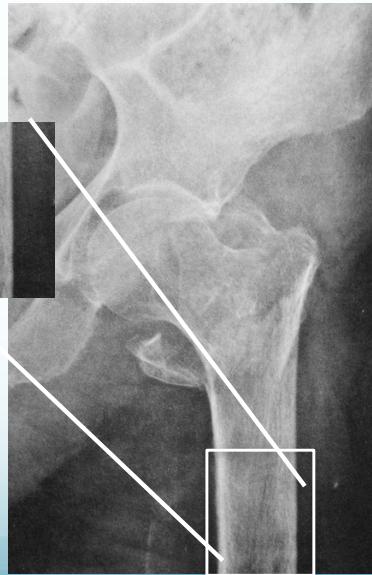

Common Fracture Sites â

- Neck of femur (has many complications)